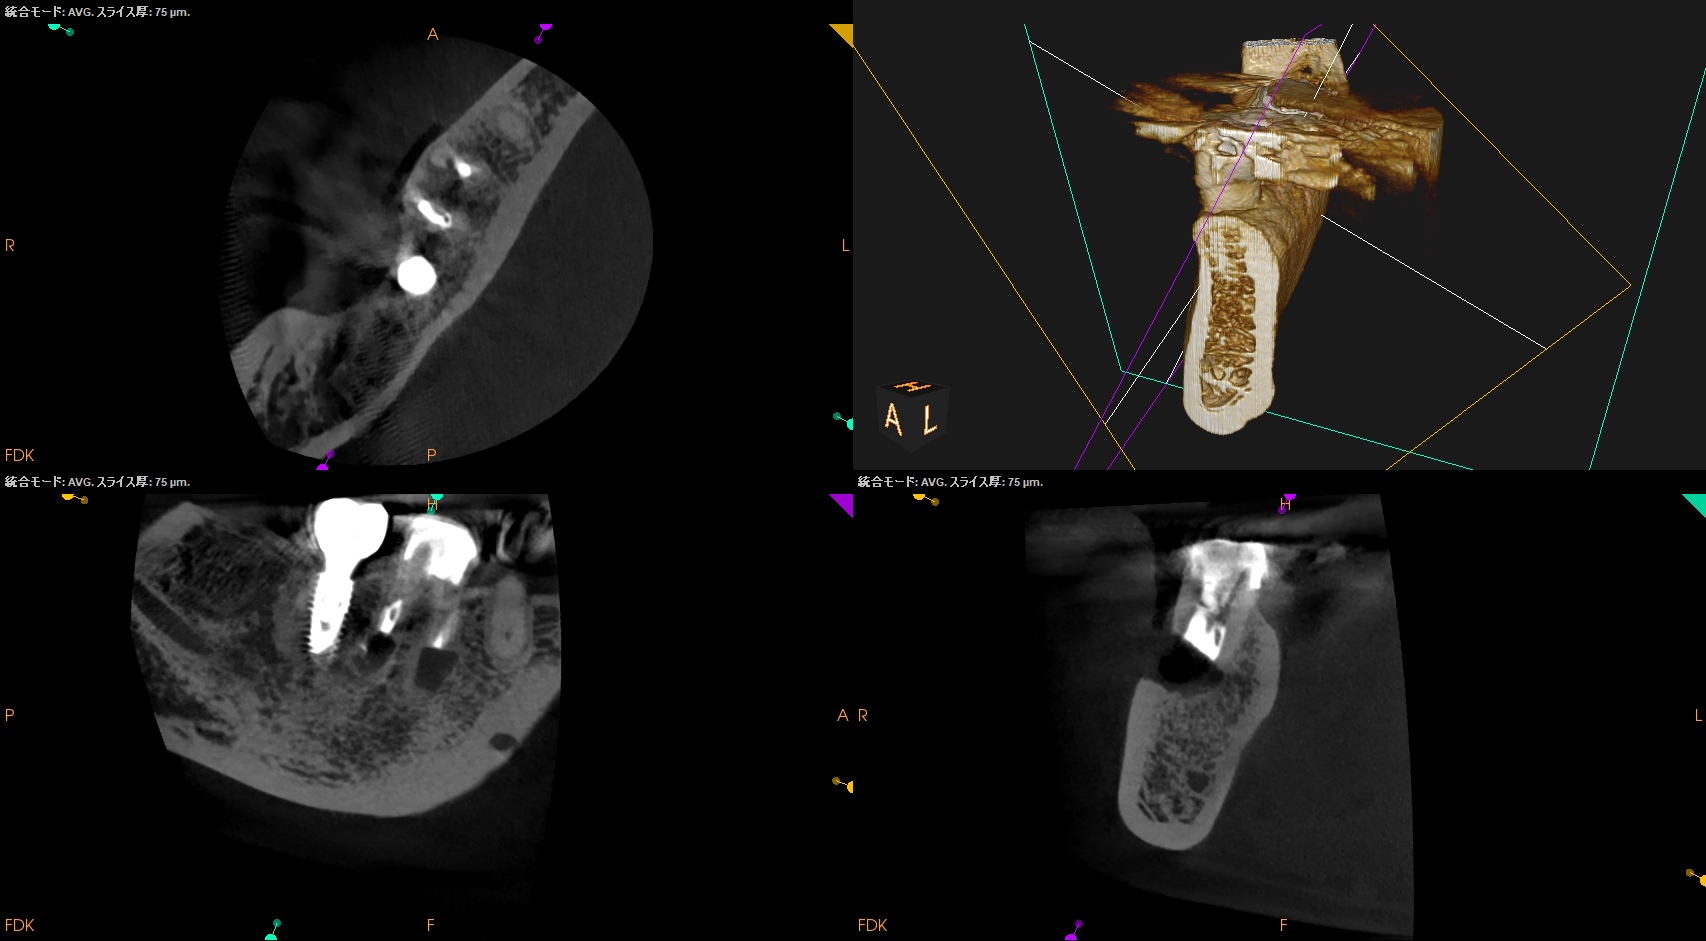

CBCT(2025.10.27)

MB

ML

DB

DL

MのApexに到達するにはCEJよりも12.5mm下方の歯槽骨を2mm削合(Osteotomy)しなければならない。

Apexを見つけたら3mm切断するがこの時の頬舌的な幅径が6.3mmだ。

リンデマンバーの半分よりも長い。

またDはApexに到達するには、CEJよりも13mm下方の歯槽骨を3mm削合する必要がある。